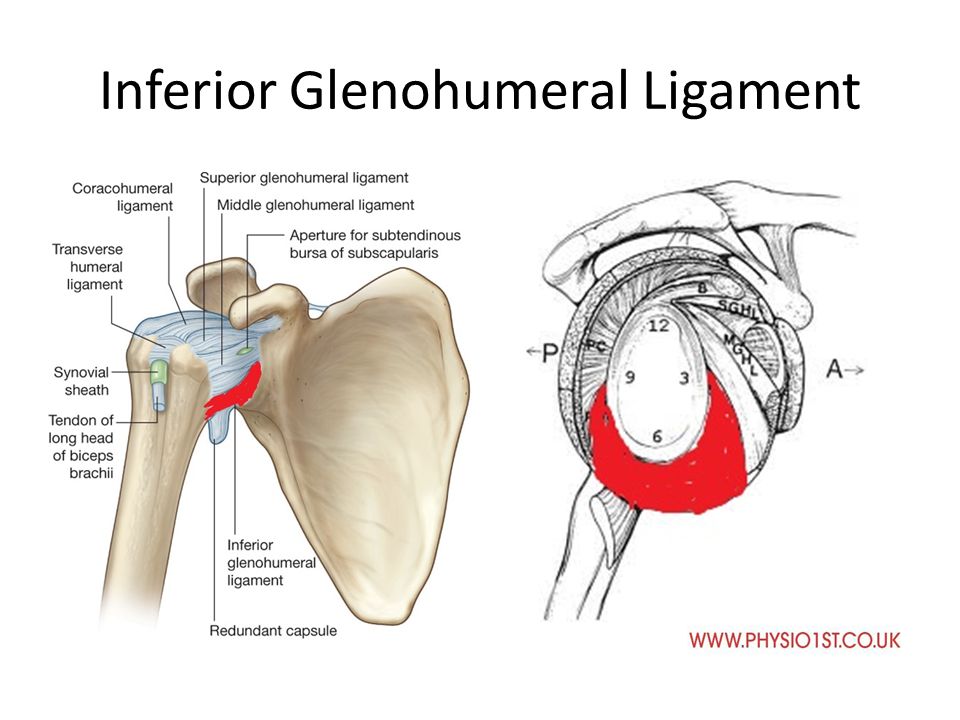

Glenohumeral ligament: анатомия и функции плечевого сустава